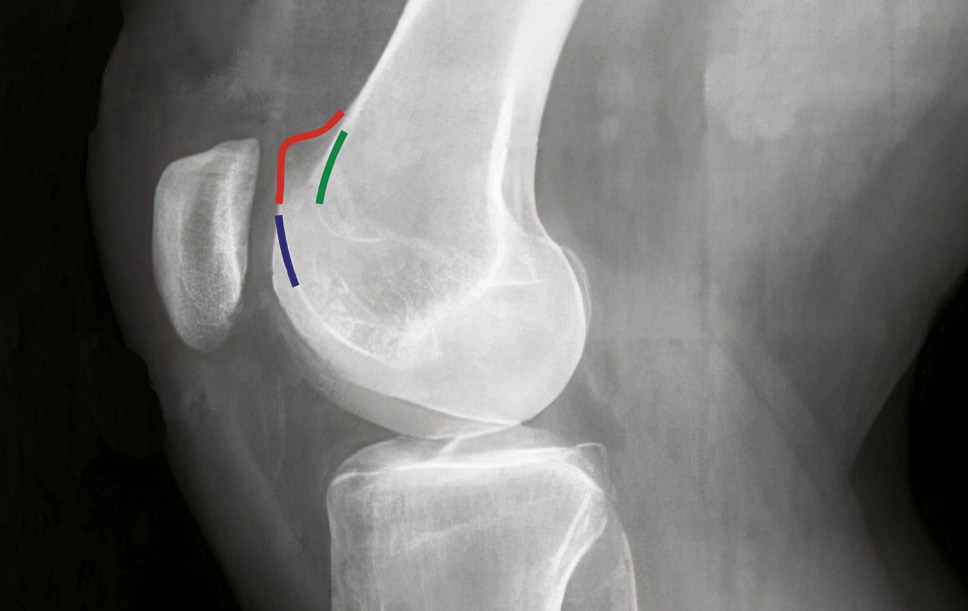

The most important and commonly observed manifestation of knee joint dysplasia, which predisposes to patellar instability and creates difficulties in its correction, is the anomalous shape of the articular surface of the femoral block. This pathology is specifically understood as "knee joint dysplasia" in the narrow sense. The diagnosis of this anatomical feature is based on the analysis of knee joint X-rays in the strictly lateral projection [9, 16, 25, 26] (Fig. 3).

Fig. 3. X-ray of the knee joint with signs of trochlear dysplasia in the lateral projection:

blue line — «crossing sign», representing the deepest point of the trochlear groove crossing the anterior border of the femoral condyles; red line — «supratrochlear spur», the prominence of the trochlea on the anterior side of the femoral cortex; green line — «double contour», hypoplastic medial facet located behind the lateral facet

Bone plastic surgeries

In 1994, N. Dejour et al. identified four risk factors for the development of patellar instability: femoral trochlear dysplasia, quadriceps dysplasia with a lateral tilt of the patella greater than 20°, a high-riding patella with a Caton-Deschamps index greater than 1.2, and excessive lateralization of the tibial tubercle with a TT-TG index greater than 20 mm. They classified femoral trochlear dysplasia based on lateral radiographic signs, including "crossing sign," "trochlear spur," which protrudes more than 3 mm above the anterior surface of the femoral diaphysis, and shallow trochlear groove with a depth reduction of 4 mm or more (see Figure 3). They also associated anatomical anomalies predisposing to lateral patellar instability with changes in the rotational profile of the lower limbs, such as excessive internal rotation of the femoral condyles more than 25° and external torsion of the tibia more than 35° [8, 9, 28, 56].